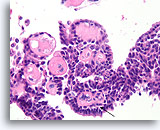

Papilloom, Borst FNA, Celblok.

Deze afbeelding van dezelfde FNA als in afbeelding 18 bevat een duidelijk papillaire architectuur.

10X

Papilloom, Borst FNA, Celblok.

Deze afbeelding van dezelfde FNA als in afbeelding 18 bevat een duidelijk papillaire architectuur.

10X

Papilloom, Borst FNA, Celblok.

Met een sterkere vergroting kan een gemengde celpopulatie gezien worden die het oppervlak en de onderliggende melkgangen bekleden. Een rij myoepitheliale cellen is zichtbaar tussen de ductale cellen en het onderliggende stroma (pijl). Let op de spleetachtige ruimte die kenmerkend is voor typische hyperplasie (open pijl).

40X

Papilloom, Borst FNA, Celblok.

Met een sterkere vergroting kan een gemengde celpopulatie gezien worden die het oppervlak en de onderliggende melkgangen bekleden. Een rij myoepitheliale cellen is zichtbaar tussen de ductale cellen en het onderliggende stroma (pijl). Let op de spleetachtige ruimte die kenmerkend is voor typische hyperplasie (open pijl).

40X

Papilloom, Borst FNA, Celblok.

Let op de bijmenging van bleke myoepitheliale cellen (pijlen) en de rijping van de ductale cellen wanneer zij zich verder van het basaalmembraan stratificeren (open pijl).

40X

Papilloom, Borst FNA, Celblok.

Let op de bijmenging van bleke myoepitheliale cellen (pijlen) en de rijping van de ductale cellen wanneer zij zich verder van het basaalmembraan stratificeren (open pijl).

40X